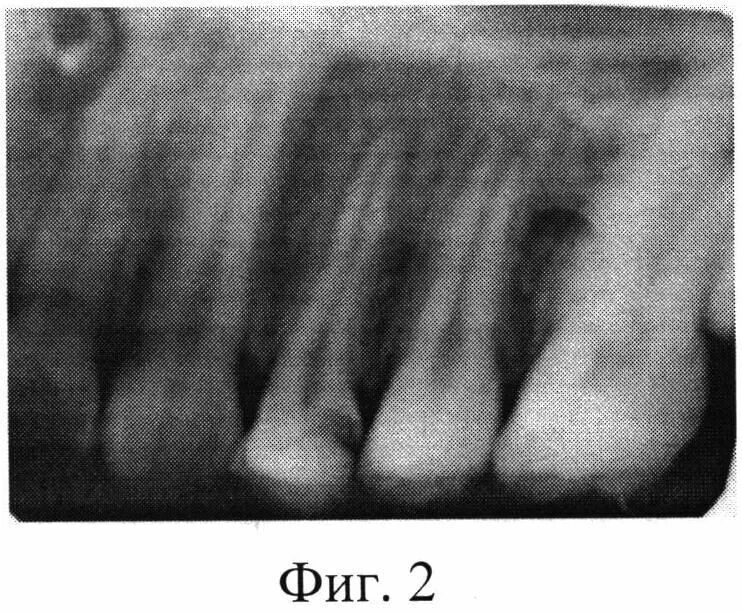

Лечение пульпита с несформированными